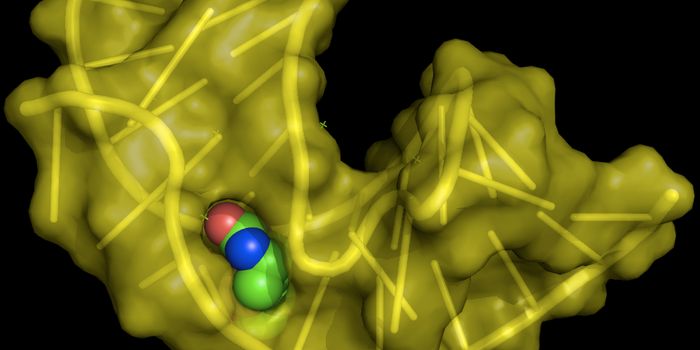

FEB 21, 2023Cell & Molecular BiologyThe Griffith Lab at UNC discovered telomeric protein & potential biomarker VR (green), shown in the nuclei (blue) of hum ...